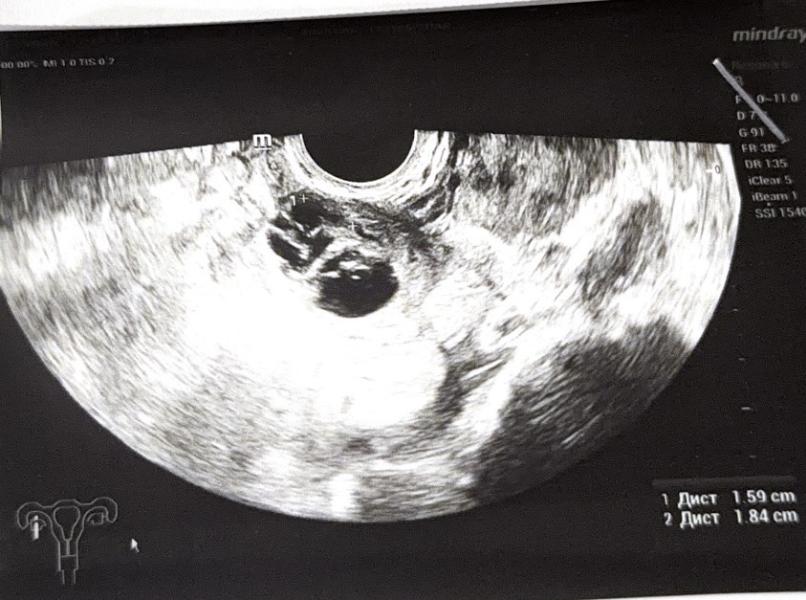

Вчера пошла на узи, 23 дц, сказали, что есть желтое тело 17мм и рядом киста, эндометриоидная, размером 18х16,

1 фото узи вчера, 2 фото узи сегодня